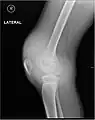

| 在脛骨平臺的微小骨折患者發現關節積血及脂肪(lipohemarthrosis,關節腔內有血及脂肪)。箭頭指出上層脂肪和下層血液成份間的液面。 | |